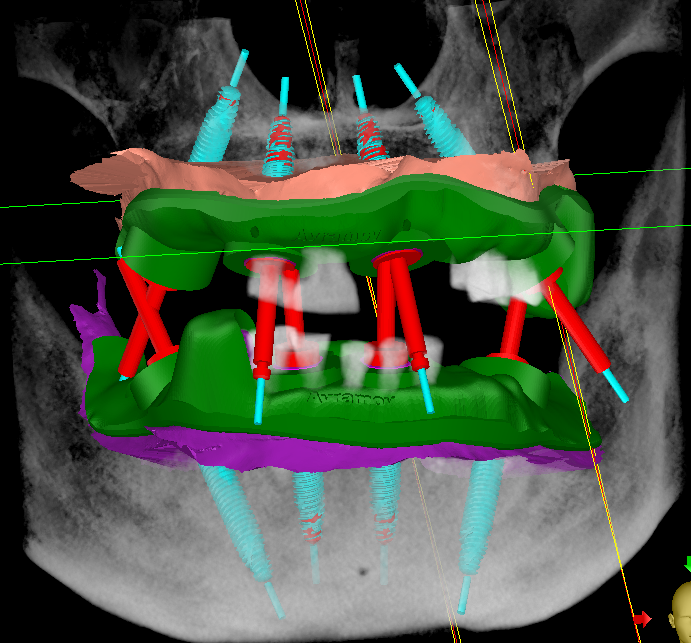

All on 6 – NeoDentЛікаріAll on 6 – NeoDentПроблема

Рухливість та відсутність зубів, хронічний генералізований парадонтит 2-3 ст важкості

РішенняІмпалнатція по системі All on 6 NeoDent та установка цирконієвих протезів на титанових балках

Термін лікування4 місяці

Вартість- All on 6 138 000 грн

- Импланты Neodent 0 грн

- Протезирование на имплантах 175 000 грн